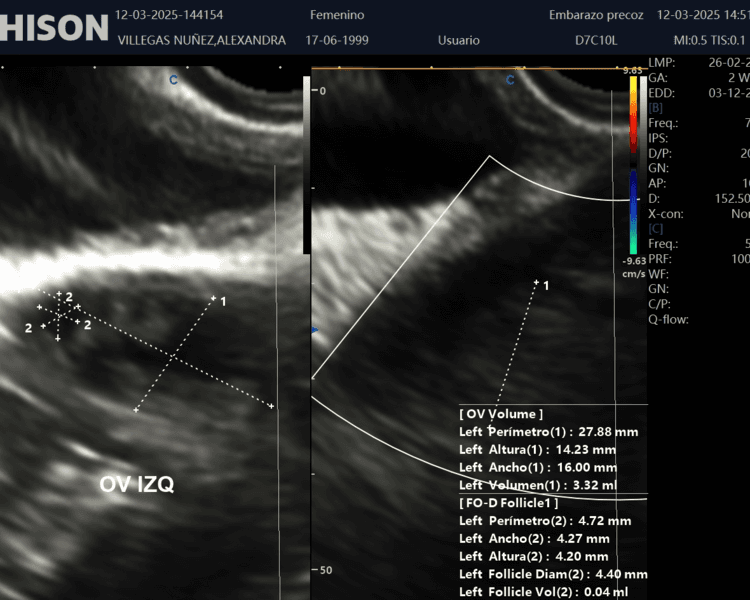

La Ecografía Ginecológica es un examen no invasivo que permite evaluar la salud del sistema reproductivo femenino. A través de ondas sonoras, se obtiene una imagen detallada de los órganos reproductivos, como el útero, ovarios y trompas de Falopio. Este estudio es fundamental para diagnosticar afecciones como quistes, miomas, endometriosis o problemas hormonales, además de ser clave en el seguimiento de tratamientos de fertilidad. ¡Confía en nosotros para cuidar tu salud ginecológica con precisión y comodidad!